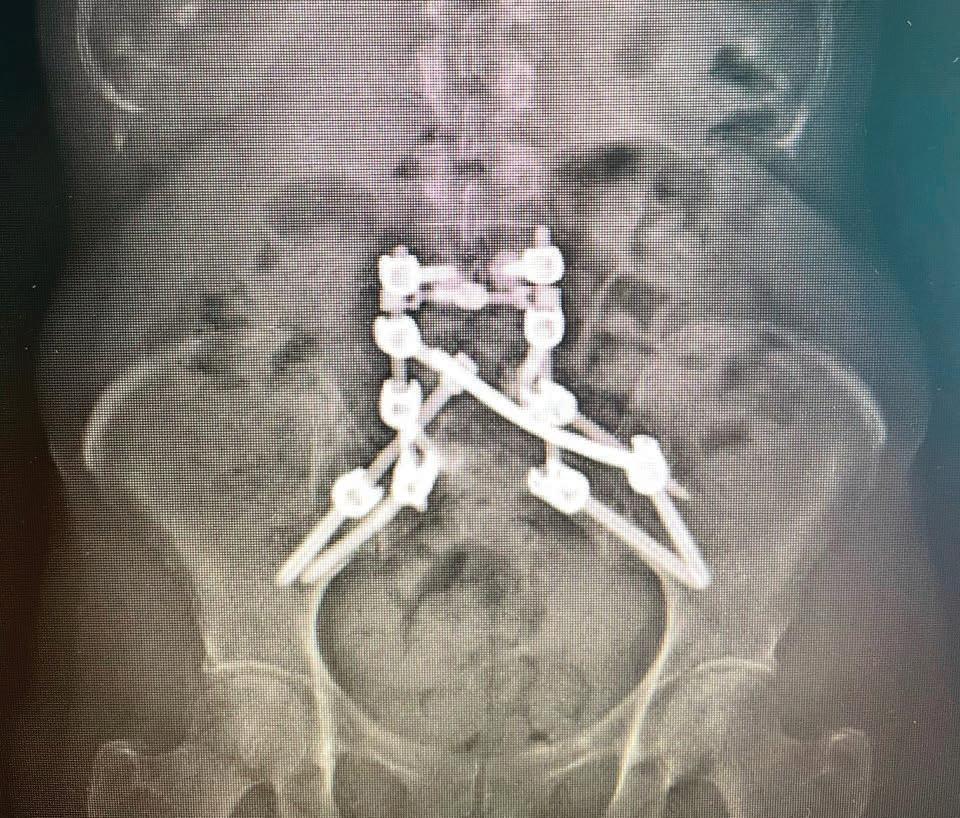

Au tour du Dr Zhi Wang, orthopédiste spécialisé en chirurgie du rachis (de la colonne), de se charger de son dossier après une discussion de cas en réunion multidisciplinaire. Après des examens complémentaires, le Dr Wang lui propose une opération rare et complexe visant à reconstruire son bassin. En octobre 2021, c’est le grand jour. On ôte une partie des métastases et on enlève la pression sur des nerfs. Ensuite, on utilise une technologie avancée pour reconstruire le bassin. Vis, tiges, connecteurs et ciment médical assurent la solidité du travail… Toute une intervention, qui prend plusieurs heures à réaliser! Mais qui se déroule très bien.

Radiographie prise après l’intervention chirurgicale. En blanc, les éléments utilisés pour reconstruire le bassin de Lyne Goulet.